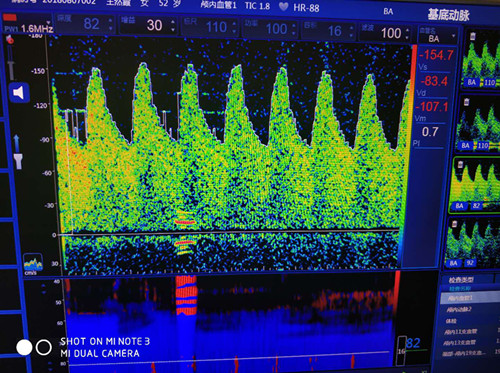

基底動脈血流速度增高